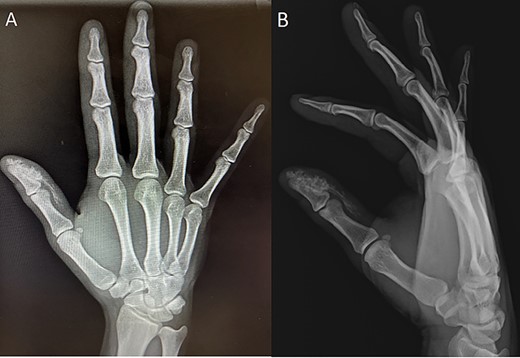

Initial injury radiographs; anterior–posterior (A) and lateral (B) radiographs of initial injury showing radiopaque material at the distal phalanx.

a high pressure injection injury with latex based paint to his right thumb secondary to a device malfunction. The patient was initially seen by providers at an outside facility and discharged on oral antibiotics. However, he presented at our facility 30 h after the initial injury with the inability to move his thumb due to significantly increased swelling and pain. Upon initial inspection, there was a 1-ml penetrating injury to the distal thumb (see Fig. 1). Initial X-rays demonstrated a radiopaque substance at the distal end of the right thumb coursing proximally without invasion of the tendon sheath (see Fig. 2A and B). The patient underwent emergent surgical incision, irrigation and debridement of the underlying tissues (see Fig. 3). Cultures were taken at the time of surgery and grew carbapenemase resistant Pseudomonas aeruginosa after 2 days. The patient was prescribed amoxicillin/clavulanate and ciprofloxacin for 7 days to provide appropriate coverage of the organisms isolated. The patient returned to clinic 1 week later where expressible paint material was found draining from the wound (see Fig. 4). The patient was admitted to the hospital and underwent a second I&D. Cultures taken at this time were negative for bacterial growth. The patient was discharged on amoxicillin/clavulanate and ciprofloxacin for 10 days. At 4 months, the wound was well healed with no signs of infection (see Fig. 5).